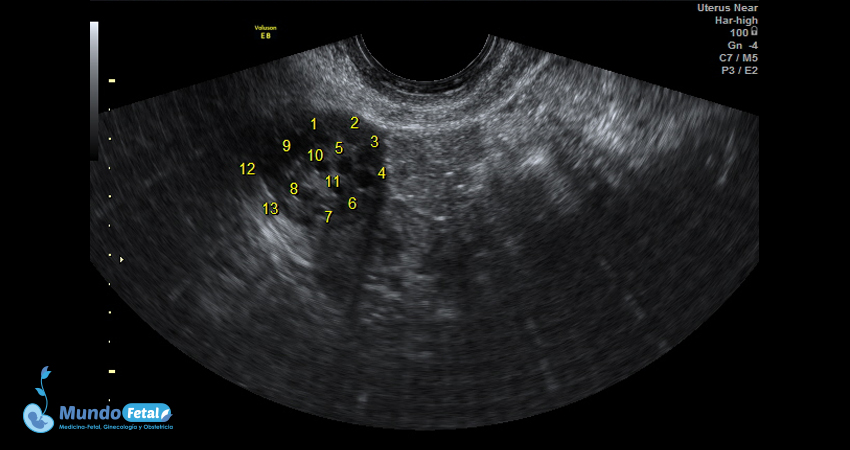

Ultrasonido Pélvico

Estudio anatómico de la región pélvica, que brinda información precisa de (vagina, cérvix, útero, endometrio, trompas de Falopio, ovarios y sus tejidos anexos) de cada uno, descartando alguna complicación de estas estructuras.